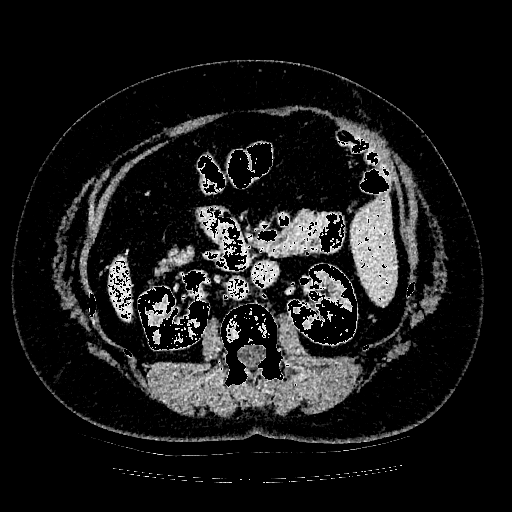

Domain change indicates that the evaluation set is derived from a different modality compared with the train set. We evaluate our model on remote sensing and medical imaging tasks. For remote sensing, we random sample 200 images and corresponding masks from the mapping challenge and denote it as the Remote-200 dataset. For medical imaging, we random sample 500 images and corresponding masks from Liver Tumor Segmentation Challenge and denote it as LiTS-500.

In this experiment, we train our model on COCO+LVIS [16, 7] and evaluate the performance on Remote-200 and LiTS-500, respectively. In this case, the data domains are completely different between training and testing.

Table 2 shows the adaptation performance of different methods on the two datasets, where ADM denotes whether the model uses the ADM part or not, and Optim denotes whether the model uses the optimization strategy. Note that, if the model does not use either ADM or Optim, it can be regarded as the off-the-shelf method, e.g. RITM. If the model uses Optim, it can be regarded as previous on-the-fly methods. As we can see, our RAIS models with both proposed ADM and Optim show the best performance compared to other methods, which means our method is more robust to domain changes. An interesting observation is that the performance deteriorates with only the ADM part. It means that although the learning ability of the model is becoming stronger with extra components, the adaptability would not get better with it. Thus, A specific adaptation module with a well-designed optimization strategy is necessary for the interactive segmentation model. Furthermore, we show the samples of visual comparison on Remote-200 and LiTS-500 in Figure 4. As we can see, the test images in remote sensing and medical images are much different from the training set, i.e. COO + LVIS. The previous method cannot handle the image annotation with the domain changes, while our method with the well-designed adaptation module and optimization strategy shows the much better results.